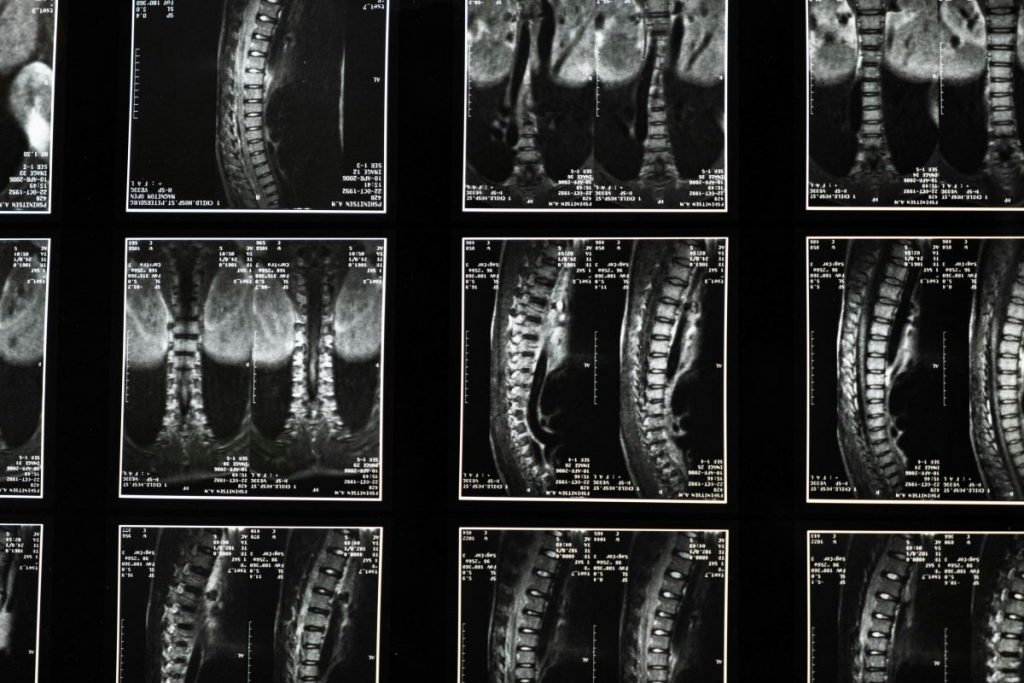

Ein zentraler Ansatz der nicht-operativen Schmerztherapie ist die präzise Diagnostik. Schmerzen entstehen häufig nicht isoliert, sondern sind Ausdruck funktioneller Störungen, muskulärer Dysbalancen oder degenerativer Veränderungen an Gelenken, Sehnen oder der Wirbelsäule. Moderne bildgebende Verfahren und eine sorgfältige klinische Untersuchung ermöglichen es, die tatsächliche Ursache der Beschwerden zu identifizieren. Erst auf dieser Basis kann eine nachhaltige Therapie erfolgen, die nicht nur kurzfristig Symptome lindert, sondern langfristig wirkt.